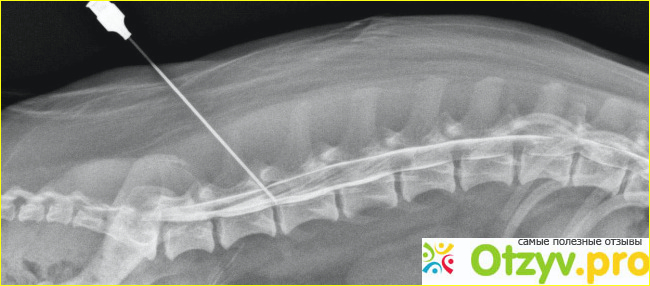

Для снятия боли при остеохондрозе используют блокаду. Такие инъекции делают именно на месте воспаления. Паравертебральный блок выполняется в определенных точках около позвоночника. Инъекция вводится в мягкие ткани, которые окружают сам нерв, или в углубления, которые расположенны в районе межпозвонковых суставов. Эпидуральная блокада делается только в межпозвоночном диске. Такая процедура является достаточно сложной и поэтому, для ее проведения необходимы знания и определенный опыт. Уколы анальгетиков облегчают боль, но они не приводят к выздоровлению. Чтобы вылечить болезнь, необходимо пройти полное лечение.

Обезболивающие при остеохондрозе: таблетки, уколы, пластыри. Блокады позволяют быстро устранить боль и уменьшить воспаление. Блокада остеохондроза дает долгосрочные результаты, однако это не считается лечением, но только снимает боль. Остеохондроз цервикальной блокады необходим, чтобы очень осторожно не повредить вены, артерии, волокна нервов. Процедура должна выполняться опытным врачом.